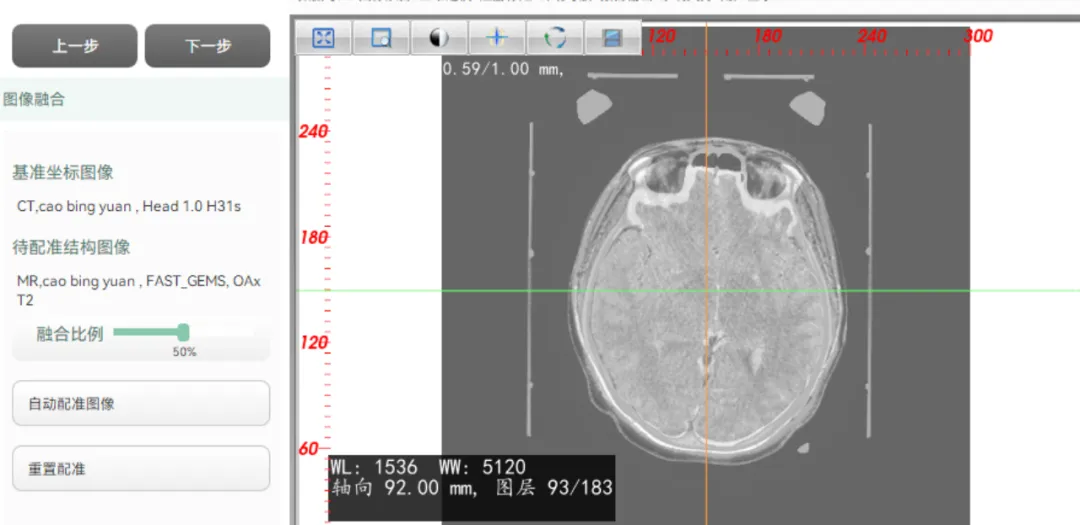

图像融合

导入多个序列,可对图像进行一键融合,生成融合序列,如:进行CT、磁共振融合,设定融合比例,可对CT或磁共振显示的权重进行调整。

0% 50% 100%